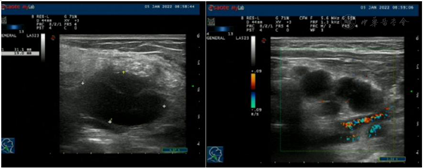

实验室提示白细胞(WBC)16.33×109/L,中性粒细胞比率(NE%)76.7 %,血红蛋白(HGB) 105 g/L,嗜酸性粒性粒细胞0.89×109/L。抗IFN-γ抗体滴度治疗期间三次复查均高于1:100。血T-SPOT试验结果为不确定。HIV(-)。痰涂片找分枝杆菌×3次阴性。右侧颈部淋巴结活检病理高通量宏基因测序检测见波斯分枝杆菌属,序列数352;痰及右侧颈部淋巴结活检组织培养及鉴定提示堪萨斯分枝杆菌生长;右侧锁骨上淋巴结脓液病理高通量测序检测见马尔尼菲蓝状菌感染,序列5149;支冲液高通量测序检测见马尔尼菲蓝状菌,序列1。2022年1月19日右侧颈部淋巴结病理提示其内见胶原纤维及纤维母细胞增生,个别可疑形成不良的上皮样细胞、组织细胞、中性粒细胞、淋巴细胞及浆细胞浸润。抗酸染色见个别阳性杆菌,六胺银、Warthin-Starry及PAS染色(-)(图1)。双侧颈部淋巴结彩色超声(图2、图3);胸部CT(图4、5)。

患者于入院后22 d出院,其后规范服药,2个月后复查痰、支冲液及右侧颈部淋巴结穿刺组织培养分枝杆菌、真菌、致病菌均阴性。4个月后追踪复查彩超、胸部CT提示右侧颈部、锁骨上、纵隔淋巴结均好转、缩小。